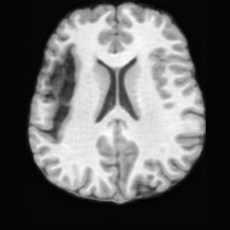

(a)PathologicalInput ImageSynthSR [18]Brain-ID [28]UNA [30]USBHealthyGround TruthRefer to captionRefer to captionRefer to captionRefer to captionRefer to captionRefer to captionRefer to captionRefer to captionRefer to captionRefer to captionRefer to captionRefer to captionRefer to captionRefer to captionRefer to captionRefer to captionRefer to captionRefer to captionRefer to captionRefer to captionRefer to captionRefer to captionRefer to captionRefer to caption(b)HealthyInput ImageConditionalLesion MaskUNA [30]USBRefer to captionRefer to captionRefer to captionRefer to captionRefer to captionRefer to captionRefer to captionRefer to captionRefer to captionRefer to captionRefer to captionRefer to captionRefer to captionRefer to captionRefer to captionRefer to caption

Figure 5: Comparison of bidirectional brain editing. (a) pathology-to-healthy, the circles and arrows highlight lesion regions and unsuccessful reconstructions; (b) healthy-to-pathology. Note that SynthSR and Brain-ID cannot perform healthy-to-pathology editing.

Pathology-to-Healthy Editing. Fig. 5 (a) presents comparison results on four input brain images with lesions of varying sizes, shapes, and densities. All competing models, although specialized for healthy brain image synthesis, struggle to reconstruct pathological regions, especially near lesion boundaries. In contrast, USB accurately reconstructs the corresponding healthy brain, even in challenging cases with large, high-density lesions where normal brain structures are almost completely obscured (last row). Tab. 2 provides a quantitative comparison for pathology-to-healthy editing, where USB achieves the best performance across all three datasets, demonstrating the effectiveness of its unified framework in reconstructing healthy brains from pathological inputs. Additional results are in Suppl. B.